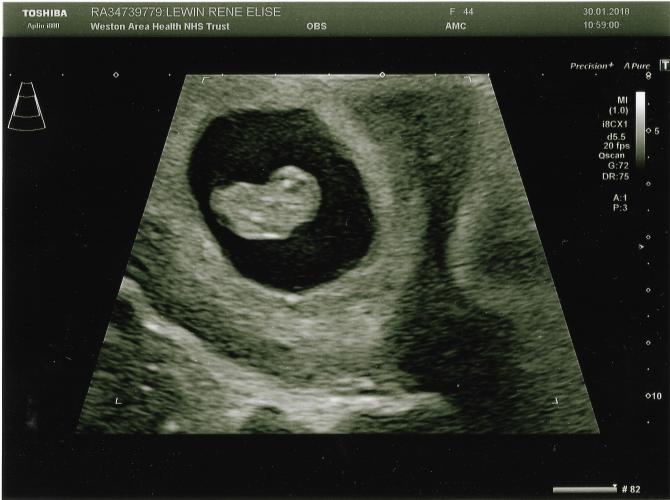

It’s taken 14 years of marriage, more heartache than I thought I could ever deal with, and some extremely expensive medical help, but a week ago we went to the hospital and were given this amazing picture.

I don’t care that it’s only 10 weeks this coming Friday. I’m going to be a daddy!

God has been telling me to pray for my children since I was 15 years old. I’ve never doubted this day would come, but I’m completely blown away that at 45 it’s finally arrived.